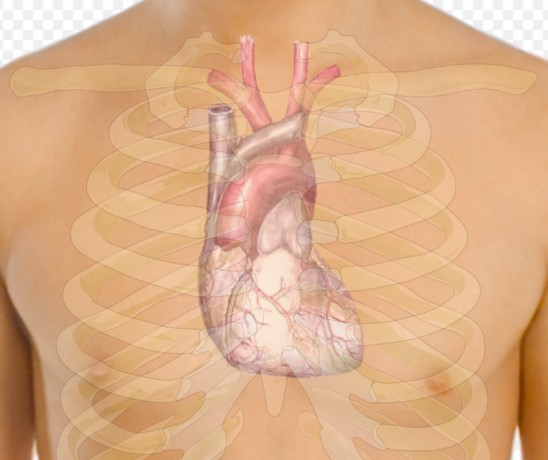

Кардиолог Ольга Бокерия сообщила, что "разрыв сердца" может произойти после инфаркта, обусловленного процессом рубцевания зоны инфаркта. Этот "разрыв" чаще всего происходит спустя 2-3 недели после инфаркта миокарда, когда стенка левого желудочка может разорваться из-за "размягчения" ткани.

Бокерия подчеркнула, что пациенты, не прошедшие реваскуляризацию зоны инфаркта, должны соблюдать постельный режим в течение четырех недель. Она также отметила, что разрыв стенки желудочка обычно является фатальным, и спасение возможно только при быстрой помощи опытных врачей с необходимым оборудованием. В редких случаях надрыв может закрыться тромбом, сообщает РИА Новости.